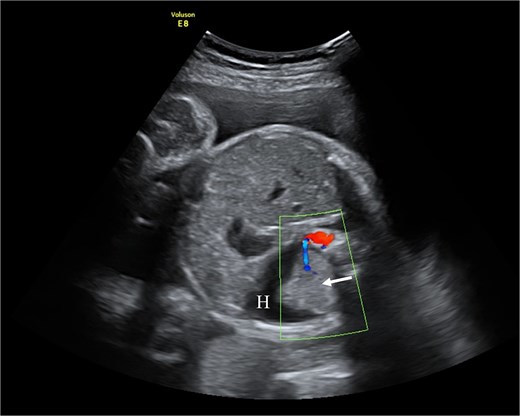

Fetal ultrasound with doppler. The arrow points to PS having a separate feeding branch from the aorta. Around sequestration the hydrothorax is present (H).

At 31 + 5 weeks, worsening hydrothorax prompted initiation of pulmonary maturation (Fig. 1). One week later, ultrasound showed bilateral hydrothorax compressing both lungs, dextrocardia, and hydrocele, indicating impending hydrops. A multidisciplinary team decided on EXIT to alleviate lung compression and facilitate breathing before cord clamping.